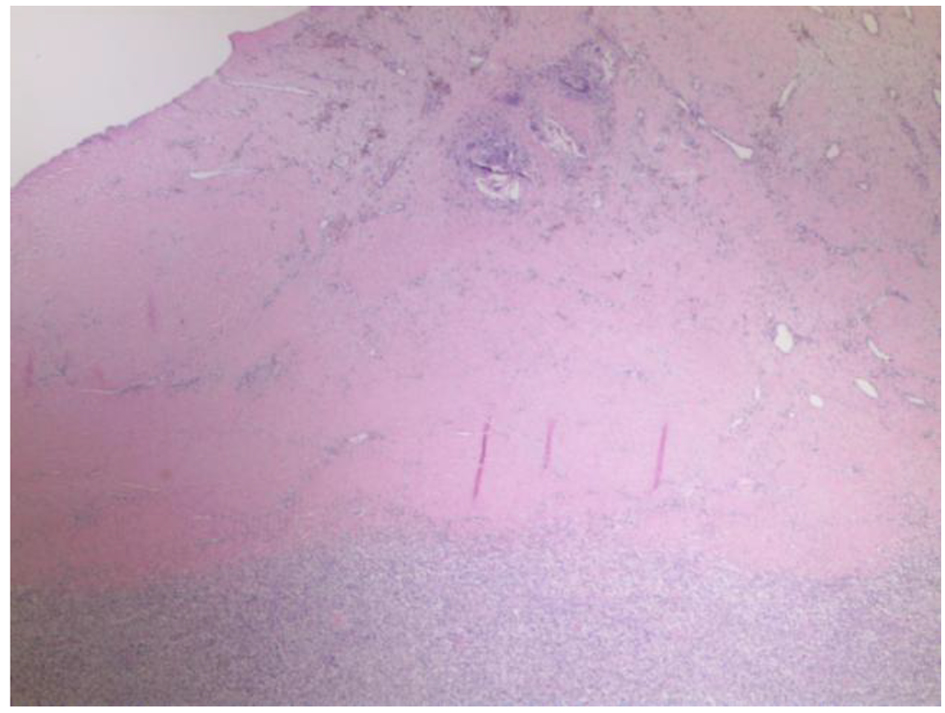

Pathological analysis of the resected tissue showed diffuse lymphoid infiltrate within fibrous tissue of medium to large atypical cells. The cells had irregular nuclei, moderate cytoplasm and conspicious nucleoli (Figs. 1 and 2). Immunohistochemistry was positive for CD20, CD10, BCL-2 and BCL-6 (Fig. 3). The findings were consistent with germinal center DLBCL. Epstein-Barr virus testing was negative. The Ki-67 proliferation index averaged 60%, but was up to 80% focally. Fluorescence in situ hybridization (FISH) was negative for BCL2/BCL-6/MYC rearrangements.

![]() Click for large image | Figure 1. Low power (× 20) image showing the reactive thick fibrosynovial tissue within the knee joint, with associated giant cell reaction to cement (top of picture) with the atypical subjacent diffuse mononuclear cell infiltrate. The differential includes both reactive/infectious conditions and malignancy. |